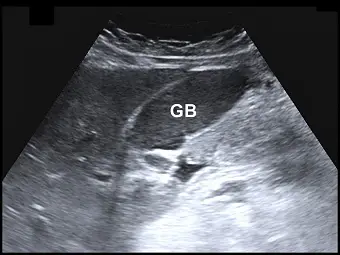

膽囊超音波掃描時,發現膽囊( GB )腔內充滿濃稠膽汁,其回音與鄰近肝臟組織的回音相近,造成膽囊不容易辨識(如圖),該現象稱之為何?

- 膽囊解剖位置(GB):影像中央標示為「GB」的區域為膽囊。

- 異常的回音強度(Echogenicity):正常情況下,膽囊內部充滿清澈的液態膽汁,在超音波影像上應呈現「無回音」(Anechoic,即黑色)的囊狀構造。然而,在此影像中,膽囊腔內完全充滿了均勻的中低度回音(Low-to-medium level echoes)。

- 等回音現象(Isoechoic):這些緻密回音的質地與亮度,幾乎與鄰近的正常肝臟實質(Liver parenchyma)完全一致。

- 邊界辨識困難:由於膽囊內容物的回音與肝臟極為相似,若非周圍隱約可見薄薄的高回音膽囊壁,整個膽囊幾乎會融入肝臟組織中,造成辨識上的困難。

- (A) 肝化(hepatization):正確。當膽囊內完全充滿濃稠的膽泥(Tumefactive sludge)或極度濃縮的膽汁時,這些物質會產